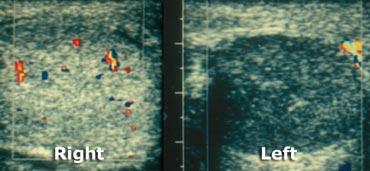

Testicular torsion: Optimal setting for color on normal side, followed by examination of symptomatic side.

Color doppler

Sự vắng mặt hoàn toàn của dòng chảy máu trong tinh hoàn và dòng chảy máu ngoài tinh hoàn bình thường trên hình ảnh Doppler màu có giá trị chẩn đoán, nếu dòng chảy ở tinh hoàn đối bên bình thường.

Tuy nhiên, sự hiện diện của dòng chảy trong tinh hoàn không loại trừ khả năng xoắn tinh hoàn, vì tắc nghẽn mạch máu không hoàn toàn đôi khi có thể xảy ra hoặc xoắn tinh hoàn ngắt quãng.

Trường hợp bên trái cho thấy xoắn tinh hoàn trái.

Trường hợp này rất rõ ràng vì không có dòng chảy ở bên bị ảnh hưởng, đồng thời cũng có sự khác biệt về độ hồi âm.

Trong trường hợp xoắn kéo dài, tinh hoàn thường giảm âm và không đồng nhất, thường kèm theo tràn dịch màng tinh hoàn xung quanh.

Khi các dấu hiệu siêu âm này xuất hiện, khả năng cứu vãn tinh hoàn bằng phẫu thuật là rất thấp.

Sử dụng đầu dò tuyến tính ít nhất 10 MHz.

Luôn bắt đầu bằng việc khảo sát bên bình thường và tối ưu hóa các cài đặt cho dòng chảy thấp, sức cản thấp và vận tốc thấp.

Nhiễu nền nên vừa đủ nhìn thấy ở tinh hoàn không có triệu chứng.

Khi đã có hình ảnh tốt của bên bình thường, không thay đổi bất kỳ cài đặt nào và chuyển sang bên có triệu chứng.